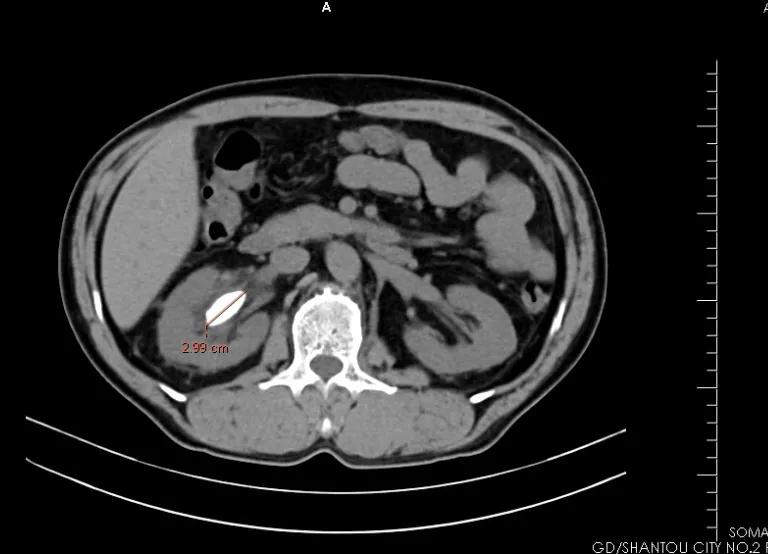

五十多岁的翁先生在体检时发现双肾有结石并有轻度积液,得知消息的时候不禁大吃一惊,平时腰腹部没有酸痛感,排尿也正常,怎么平白无故就长出了结石……为了进一步治疗,翁先生到市二医院泌尿外科门诊就诊,泌尿外科主任王乐浩对翁先生完善相关检查, CT检查提示:右肾(鹿角型)铸型结石,约 3.0*2.0*1.5cm大小,左肾小结石,膀胱小结石!

右肾铸型结石影像图片

王乐浩主任根据翁先生的情况决定采用“腰硬麻下行电子输尿管软镜联合硕通镜右肾结石腔内碎石取石术”,手术中,王主任通过一根鼠标线大小的软管,经尿道、输尿管等自然腔道,精确接近病灶,一束钬激光逐渐将直径3厘米大的铸型结石击碎,通过硕通镜负压吸引将肾盂内碎石块吸出,减少了结石移位肾脏风险。术后第3天,翁先生在泌尿外科医护人员的精心照料下痊愈出院了。